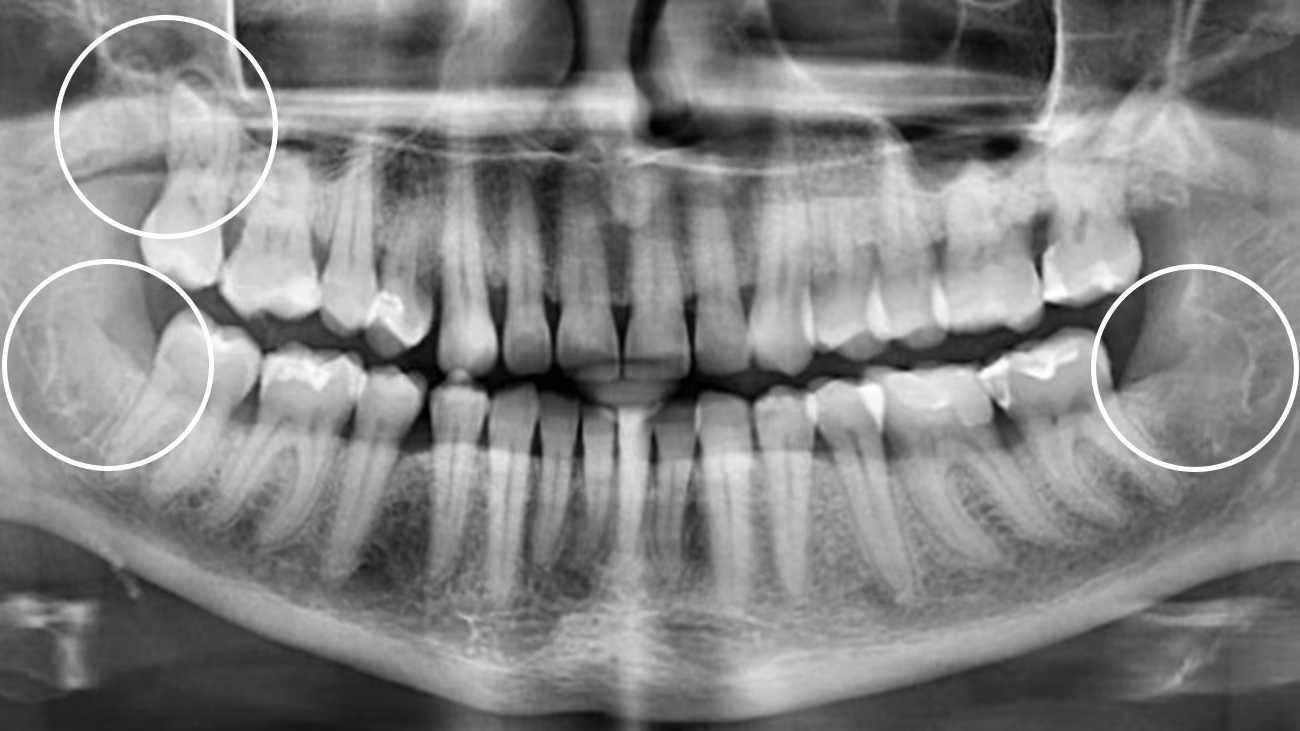

Так. КТ є обов’язковою для точного та безпечного видалення зуба мудрості.

3D-діагностика дозволяє визначити:

• положення зуба

• напрямок росту

• особливості коренів

• близькість до нижньощелепного нерва або верхньощелепної пазухи

У Sergatiy Dental Clinic КТ є обов’язковою перед видаленням зуба мудрості. Без КТ значно підвищуються ризики ускладнень.